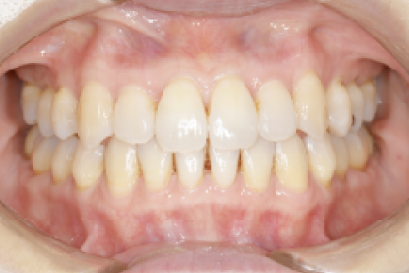

• 症例4

術前

*

術後

年代、性別

20代、男性

職業

学生

主訴

歯並び相談

部位

抜歯を併用してのインビザラインによる全顎矯正

治療期間

1年6ヶ月

矯正費用

95万円

施術説明

他院の矯正専門医院でマウスピース矯正は不可能と言われて、セカンドオピニオンで来院されました。就職活動が始まるまでに、歯並びを治療しておきたいということでしたが、当院の矯正専門医であるインビザライン・ファカルティーの山本先生による検査では、インビザラインで治療が可能と診断されました。抜歯を伴う矯正は通常長期にわたる事が多いですが、1年半で治療も完了し非常に喜んでもらえました。

副作用・リスク

なし